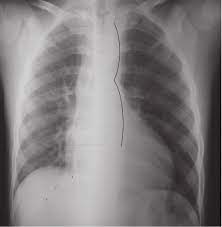

La patología vascular, esa amplia categoría de enfermedades que abarca los trastornos de los vasos sanguíneos, ya sean arterias o venas, es motivo de profunda preocupación en el ámbito…